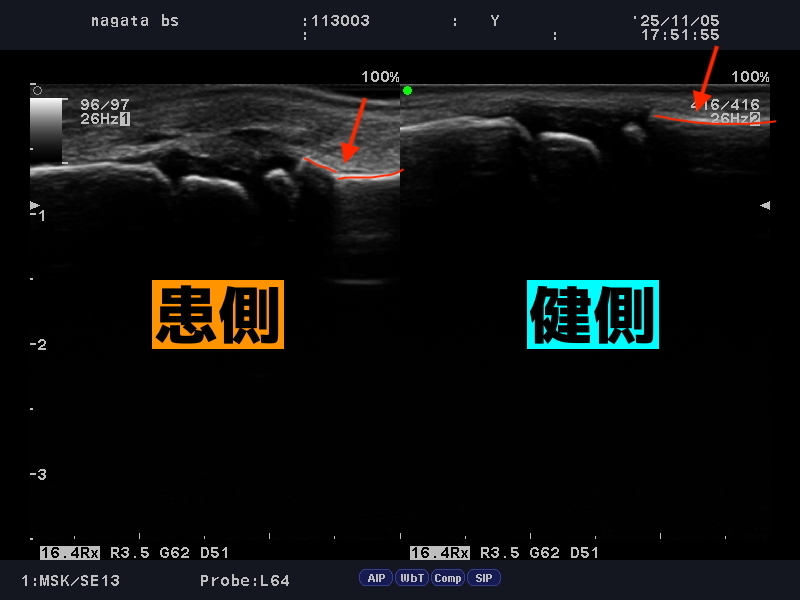

整復操作により変形が戻っています。

骨が変形するほどの骨折の場合、整復といって変形を戻す操作を行わないといけません。

今回も一度の操作で、綺麗に変形が戻りました。

骨折がわからないほど、綺麗に整復されているとお褒めの言葉をいただきました。

連携先の整形外科の先生からも、

「レントゲンでも骨折がわからないほど変形が綺麗に戻っている」

「研修医の先生なら骨折を見逃してしまうほど」

とお褒めの言葉をいただきました。ありがとうございます。